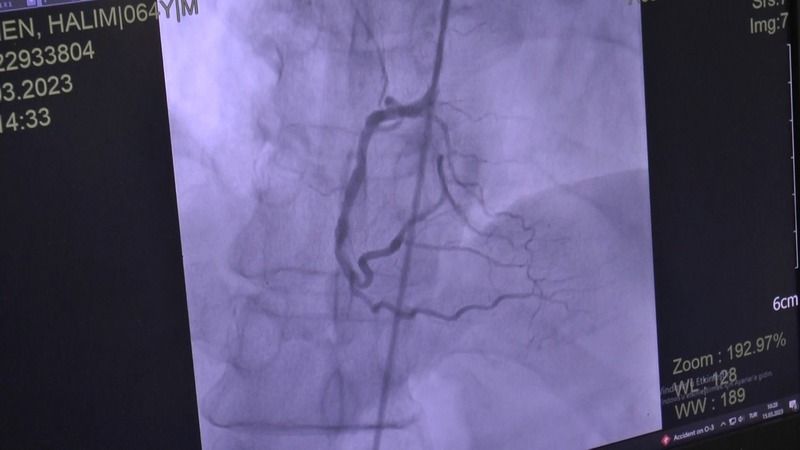

Sözlerine devam eden Doç. Dr. Hakan Çakır, “Özellikle semptomatik kardiyovasküler sistem hastalığı olanlarda oruç tutmak sakıncalı. Bilinen bir kalp yetmezliği olan bir hasta hala semptomatik nefes darlığı çekiyorsa, ciddi ödemleri varsa bu durumda oruç tutmasını önermiyoruz. Yine ileri devre kalp yetmezliği olan hastalarımız klinik olarak stabil olsalar dahi oruç tutmalarını önermiyoruz. Şah damarına stent taktığımız hastalar, stent sonrası ilk 6 ay süresince yüksek riskli dönemde oluyorlar. Bu hastalarımızın da işlem sonrası ilk 6 ay içerisinde oruç tutmasını önermiyoruz. Önemli konulardan biri olan dirençli hipertansiyon hastalarımızda oruç tutmalarını önermediğimiz gruplar arasında” diye konuştu.